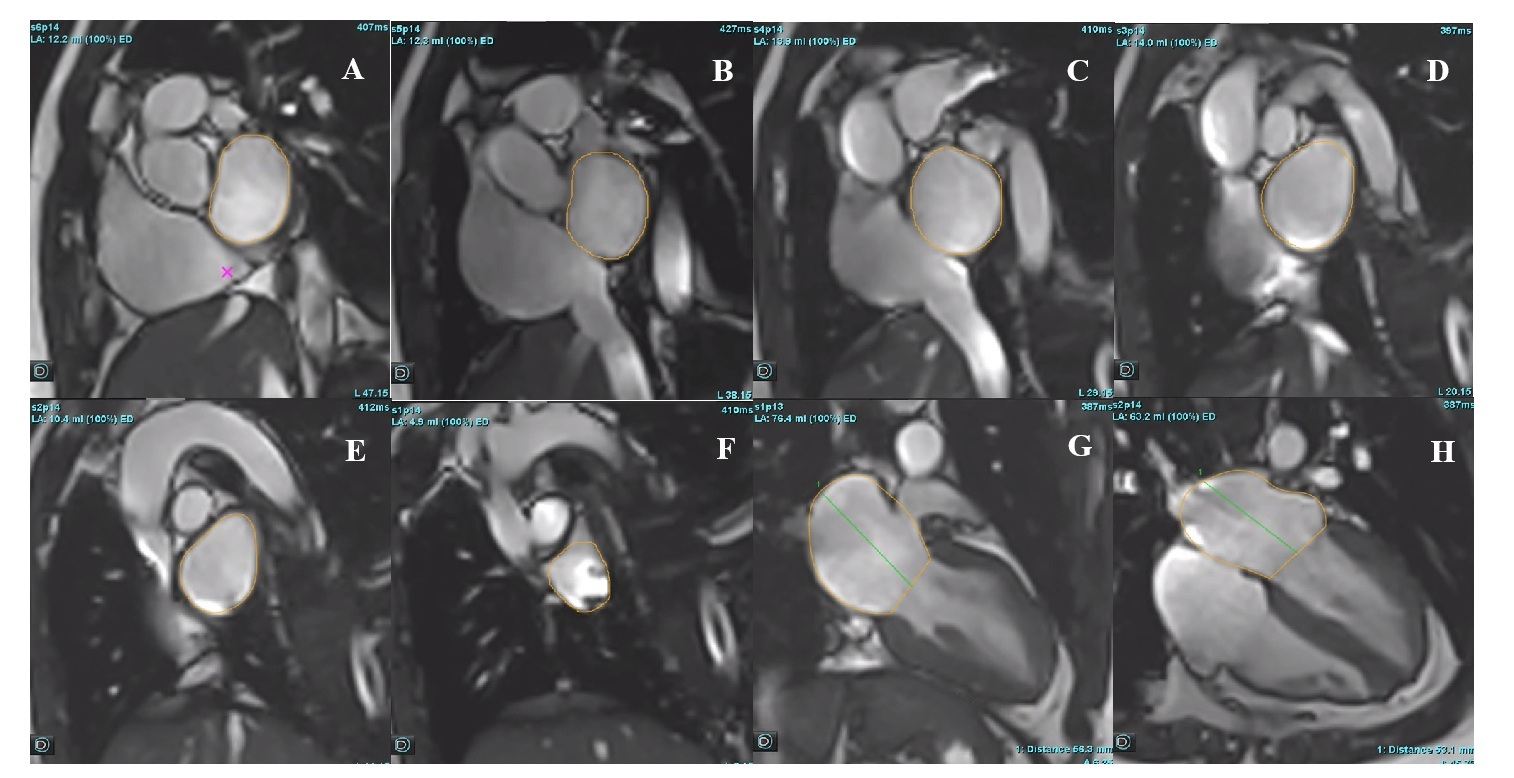

Methods | Robust r value | Spearman rho value | P value | Difference from V Simpson-SAX (mean±SD, ml) |

V Simpson-LAX | 0.904 | 0.377 | 0.204 | 17±5 |

VAL | 0.922 | 0.423 | 0.150 | 15±3 |

VSAX AL | 0.952 | 0.791 | 0.001 | 13±3 |

Figure 2: Bland-Altman curves between V Simpson-SAX and other methods of LA volume measurement.jpg)